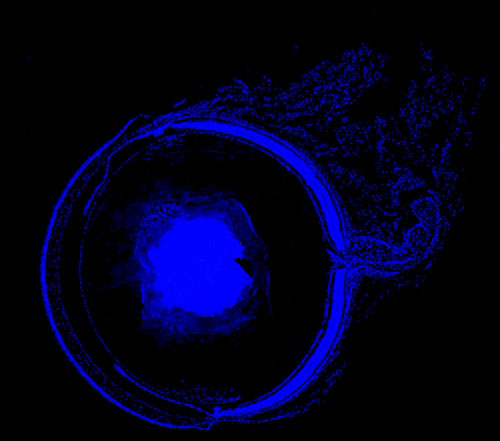

實驗結果展示:

DAPI染色-小鼠眼球